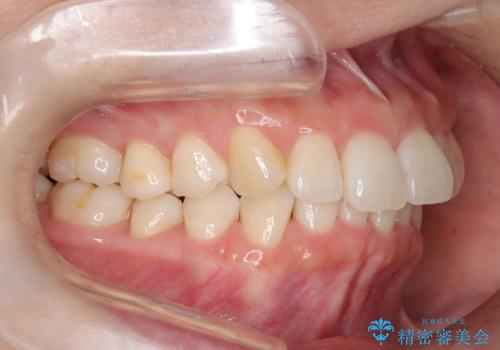

インビザライン ライトパッケージによる部分矯正治療 下の前歯のみの歯並び改善

- インビザライン ライトパッケージパーシャル(下顎のみ)

- 下の前歯の歯並びのみの改善をご希望されました。

インビザライン ライトパッケージ下顎のみ(1枚~14枚まで)での治療を行なっていきました。

マウスピース枚数 初回14枚 + 追加13枚

概ね7ヶ月で治療完了しました。

インビザラインのライトパッケージでは14枚までという枚数制限がありますが、限られた枚数の中で当院独自の工夫を随所に盛り込み、狙い通りの治療結果が得られました。